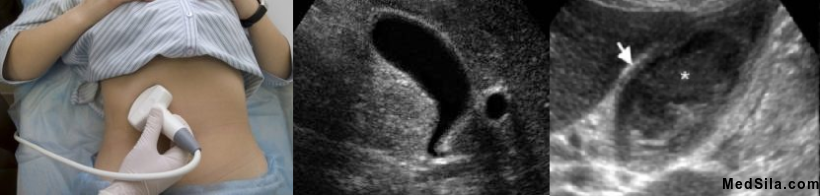

- УЗИ органов брюшной полости, которое является золотым стандартом диагностики холециститов. При данном исследовании можно обнаружить особенности строения пузыря и протоков, увеличение толщины стенок пузыря, их расслоение, наличие или отсутствие камней в пузыре и протоках, распространенность процесса, а именно не вовлечена ли в воспаление околопузырная клетчатка, состояние соседних органов и многое другое, важное для постановки диагноза и определения тактики дальнейшего лечения.